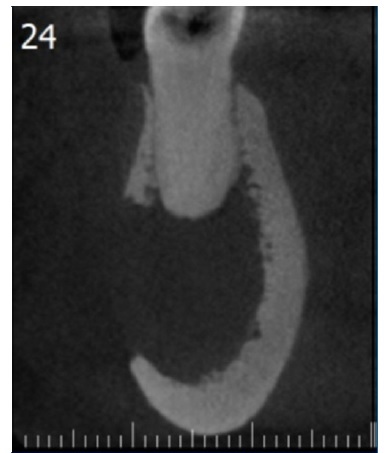

A TC (Figuras 1, 2 e 3) revelou imagem hipodensa, ostelítica, de forma ovalada, promovendo rompimento da cortical vestibular, envolvendo o ápice dos dentes 44 e 45. Nesse momento, a paciente informou ter o diagnóstico de mieloma múltiplo há sete anos, sendo acompanhada por hematologista, sem apresentar sinais clínicos da manifestação da doença.

Figura 2 Reconstrução parassagital de TC. Observa-se lesão hipodensa e osteolítica envolvendo o ápice do dente 44